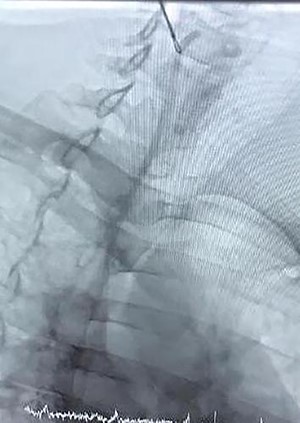

Magnetic resonance imaging was scheduled to evaluate brain metastasis. The venogram showed occlusion in the SVC. As the patient’s symptoms presented in <1 month, we passed a thrombolytic catheter through the port line, and the port was removed. Thrombolytic agent and heparin infusion were prescribed for 48 h. Repeated venogram revealed remained occlusion in SVC, so balloon venoplasty was done a day later (Fig. 2). The procedure was uncomplicated. The patient’s symptoms were remarkably improved at the time of discharge.